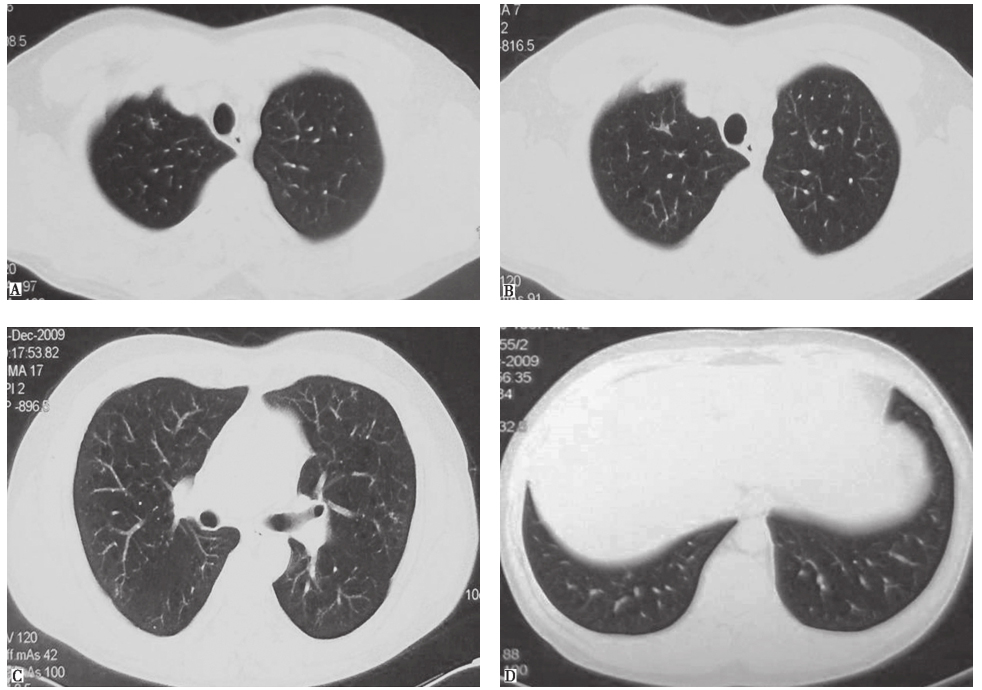

鉴于患者临床症状不重,无肺外系统受累,建议患者严格戒烟(包括被动吸烟)。患者在严格戒烟1个月后,症状逐渐减轻;3个月后复查胸部CT见双肺结节及空洞明显减少(图3);严格戒烟6个月后复查胸部CT显示双肺散在微小结节进一步减轻、减少(图4)。

图3严格戒烟3个月后复查胸部CT表现